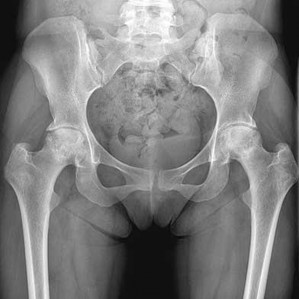

Figure 19 is an anteroposterior pelvis radiograph of a 60-year-old woman who has a 4-month history of right hip pain. She has a

medical history of lupus and has used

21

prednisone in the past, but not currently.

Her pain is persistent despite use of over-the-counter pain medications and activity modifications. What is the most appropriate treatment at this point?

This scenario describes osteonecrosis of the hip, likely attributable to chronic corticosteroid use. Her radiographs show bilateral hip involvement with whole-head involvement and collapse of the femoral head. Observation, protected weight bearing, and bisphosphonates have been advocated during the precollapse stage, but, considering the advanced

involvement of the femoral heads, these treatments are not indicated. Hip arthroplasty is the most reliable treatment option at this point to resolve her symptoms. Total hip resurfacing is not indicated for multiple reasons, including poor bone stock from corticosteroid use and her age. Large-head involvement and concerns about metal-on-metal articulation in someone with potential for renal impairment (such as a patient with lupus) also are contraindications to total hip resurfacing. Total hip arthroplasty will offer the best chance for success.